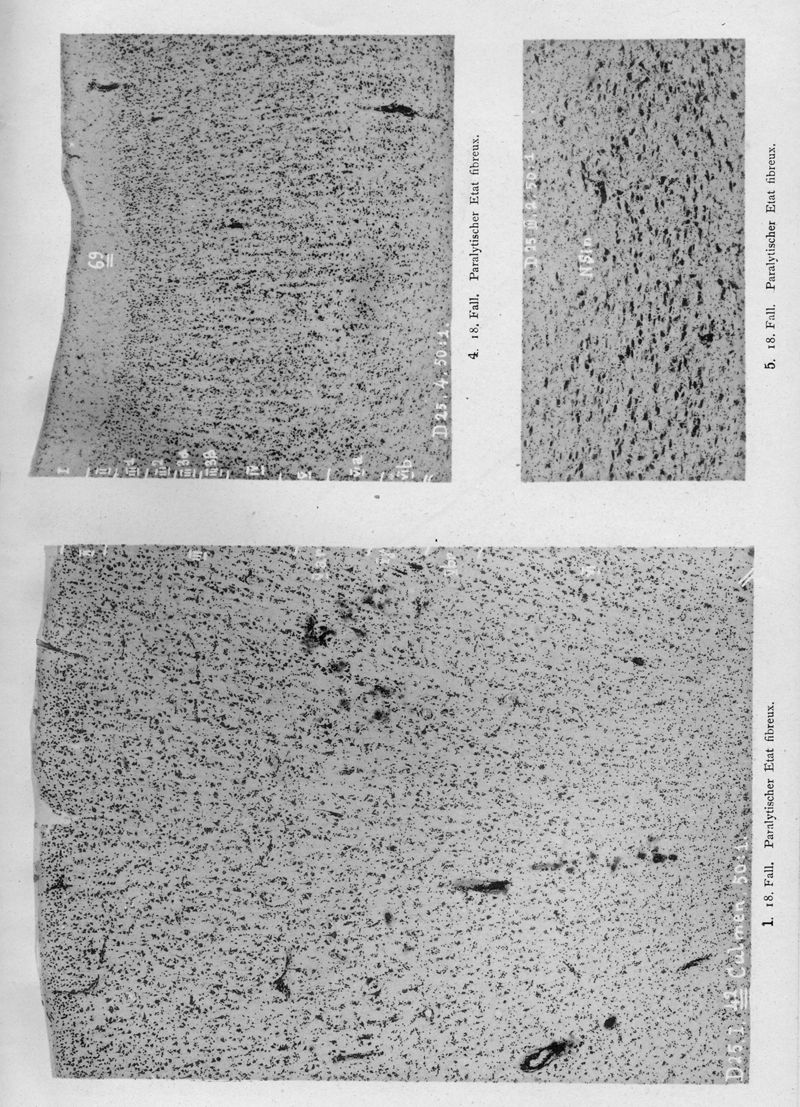

VOGT, Cécile / VOGT, O.

In : Journal für Psychologie und Neurologie,

1920, Vol. 25, pp. 627-846